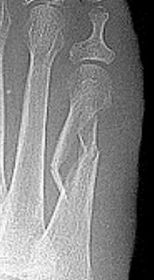

| What type of fracture is this? | Oblique fracture |